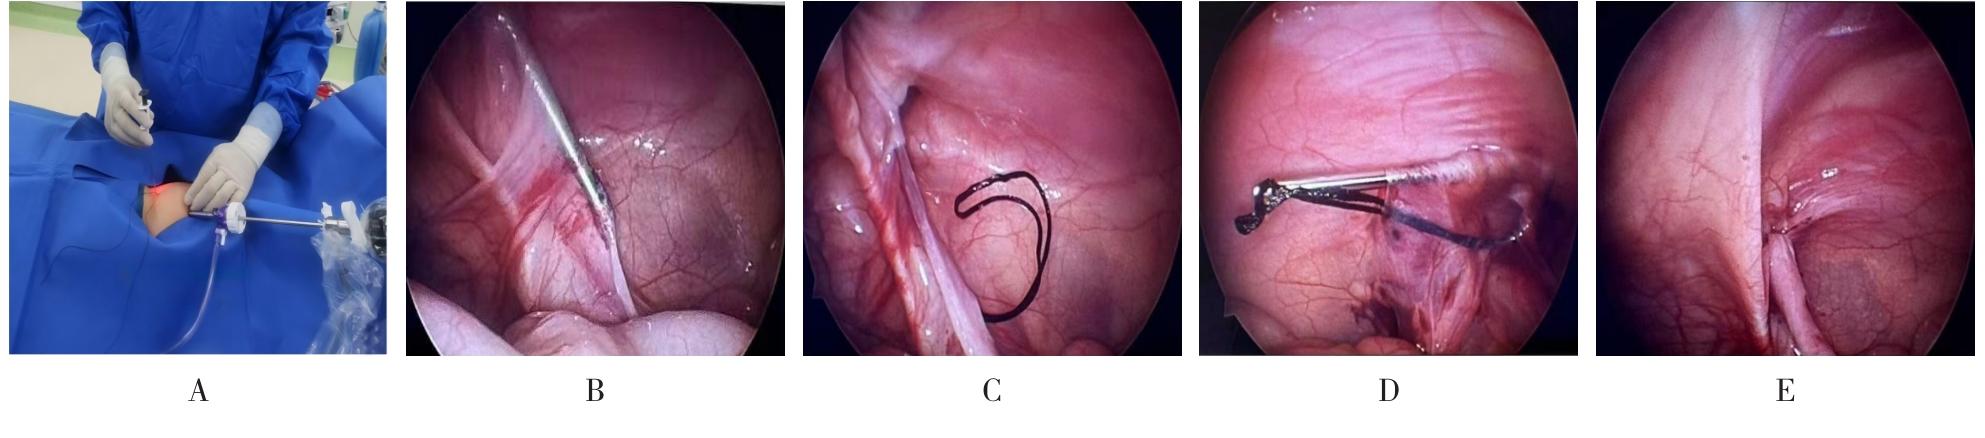

• 新型经脐腹腔镜术与常规三孔法治疗单侧巨大腹股沟斜疝的对比研究

摘要:目的 探究新型经脐腹腔镜术与常规三孔法治疗单侧巨大(≥15 mm)腹股沟斜疝的临床疗效。方法 回顾性分析2020年7月-2023年8月该院收治的213例单侧巨大(≥15 mm)腹股沟斜疝患儿的临床资料。按照手术方法不同,将患儿分为三孔组(107例,行三孔法腹腔镜疝囊高位结扎术)和新型组(106例,行新型经脐腹腔镜术)。比较两组患儿手术指标、儿童疼痛行为量表(FLACC)评分、家长对切口外观满意度、睾丸体积、术后并发症和复发率(术后1年内)。结果 新型组术中出血量和切口数量少于三孔组,切口长度、手术时间、术后切口愈合时间和住院时间短于三孔组,差异均有统计学意义(P < 0.05);术后6、12、24和48 h,新型组FLACC评分低于三孔组,差异均有统计学意义(P < 0.05);新型组患儿家长对切口外观满意度为100.00%,高于三孔组的88.79%,差异有统计学意义(P < 0.05);两组患儿术前患侧睾丸体积小于健侧,术后1年,患侧睾丸体积大于术前,差异均有统计学意义(P < 0.05);新型组术后1年健侧与患侧睾丸体积比较,差异无统计学意义(P > 0.05);两组患儿并发症总发生率和总复发率比较,差异均无统计学意义(P > 0.05)。结论 与常规三孔法比较,新型经脐腹腔镜术具有操作便捷、创伤小、疼痛轻、术后恢复快和切口美观等特点,应用于≥15 mm的单侧巨大腹股沟斜疝的治疗中,更具优势。